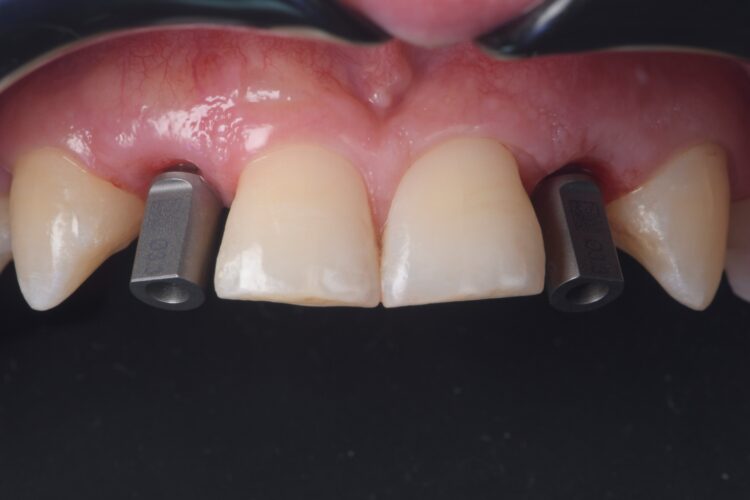

On the day of surgery, a split-thickness envelope flap was raised. Two CONELOG® Progressive-Line implants were placed through the surgical guide in the pre-determined lateral incisor positions. Soft tissue augmentation was performed simultaneously with the implant placement, and the site was sutured and closed without tension. The implants were immediately loaded using provisional crowns that were pre-fabricated in the lab.

The CONELOG implants were selected because they provide a very stable connection and feature a geometry that facilitates high primary stability, which is important when placing immediate implants. They also integrate very successfully – we have had better results with these implants than with other products that are available. I also appreciate the simplicity of the keyless guided surgery kit.

Case outcome

Both the patient and I were very happy with the outcome in this case. Given the patient’s reluctance towards excessive treatment, he was not willing to undergo any further procedures such as composite edge bonding or veneers, which could have enhanced the aesthetic result. However, he was more than satisfied with the replacement of his missing lateral incisors, and while he understands that more implants will be needed in the future when the remaining deciduous teeth are lost, he was happy to postpone that treatment for now.